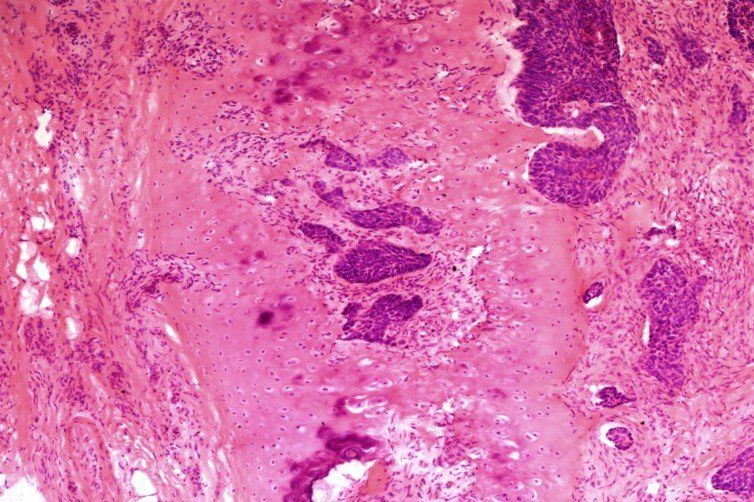

H+E - Mohs Scheme

Here's a H+E slide showing basal cell carcinmoa invasion into cartilage from tissue taken from the nasal bridge are. Marks were deducted for: Eosin intensity too string, knife marks, folds and creases. This slide scored 7/10 at assessment.